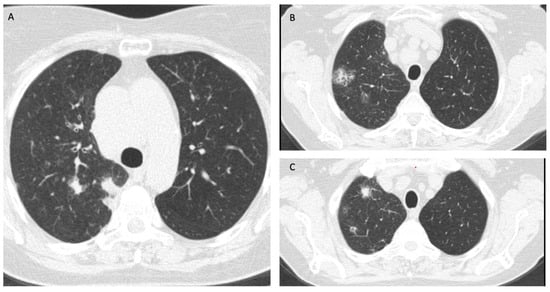

Magnetic resonance imaging (MRI) of the brain on admission showed no signs of an invasive lesion or other abnormal findings. A computed tomography (CT) scan of the chest, abdomen, and pelvis showed multiple solid lesions on the right lung (especially the upper part of the inferior lobe, the apex, and the hilum of the right lung) with surrounding ground glass regions, mediastinal and hilar lymphadenopathy (Figure 1). EBUS (endobronchial ultrasound) bronchoscopy was performed, and a biopsy of the right hilar lymph node was taken. The pathology report revealed small-sized malignant cells with scant cytoplasm staining positive for thyroid transcription factor-1 (TTF-1) and synaptophysin, which was indicative of SCLC. The Ki67 index was approximately 85%. There was evidence of extensive crush artifact and prominent necrosis. Patchy lymphocytic infiltration was evident within the tumor nests themselves, though less dense than at the periphery. Therefore, the diagnosis of limited-stage SCLC was established.

Figure 1. (AC) Multifocal deposits of SCLC in the right lung at diagnosis.